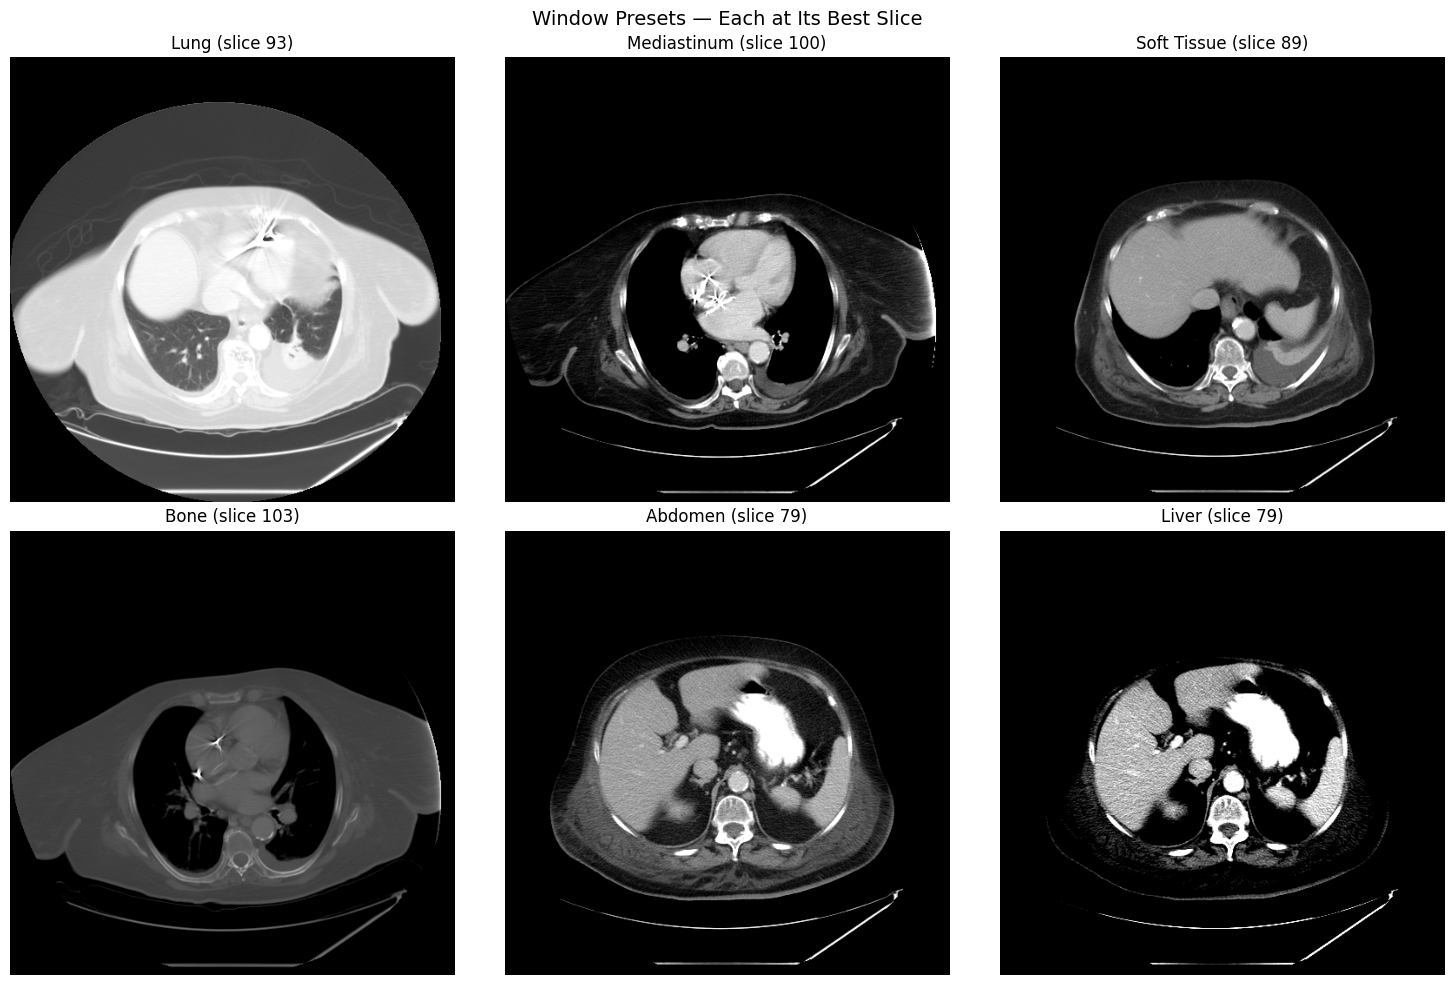

Window Preset Comparison

Different window/level settings reveal different anatomical structures. Each preset is shown on the axial slice where that anatomy is most visible:

Six window presets showing different anatomical structures